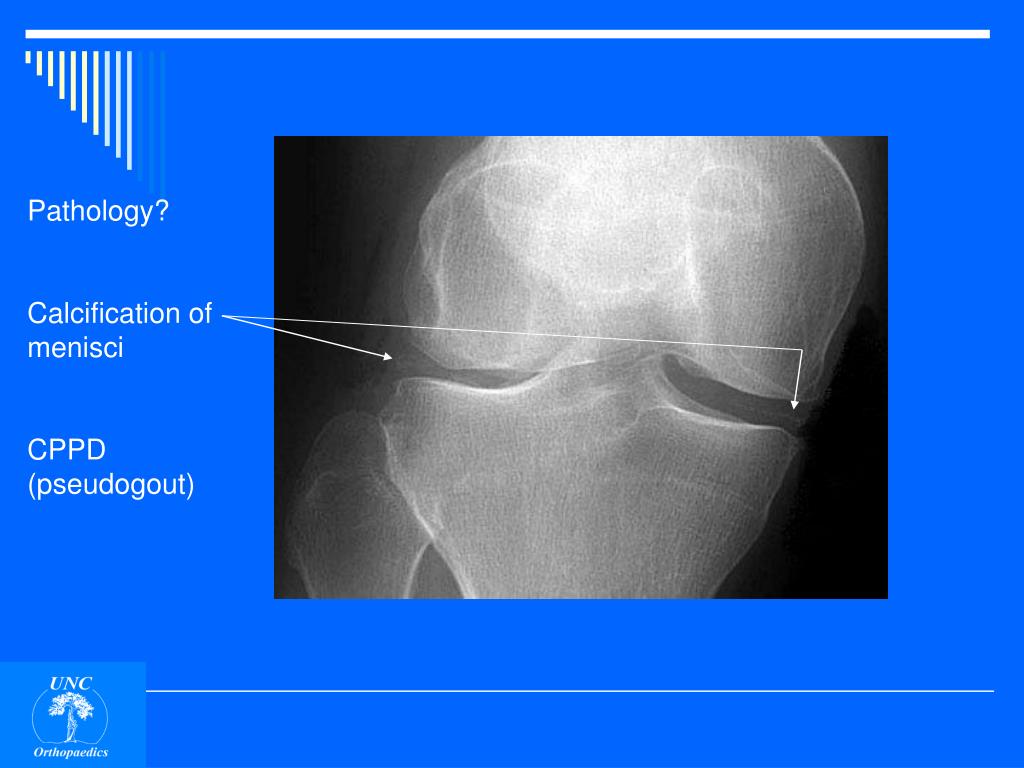

14. Pathology? Calcification of menisci

15. Pathology? Calcification of menisci CPPD (pseudogout)